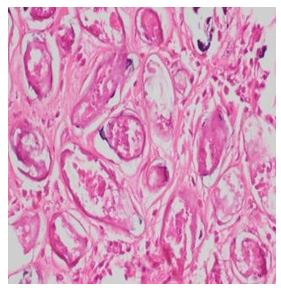

Laboratory results showed leukocytosis with significant eosino- philia. Direct stool examination revealed yeast, but stool concen- tration by the Kato Katz technique was not performed. Abdominal ultrasound was not carried out due to financial constraints. The pa- tient underwent surgery, and the appendectomy specimen was sent to the Pathology Department of CHU Renaissance. Histopatholog- ical analysis demonstrated calcified Schistosoma mansoni eggs in the lamina propria and submucosa of the appendix wall (Figure.1). The patient received praziquantel (Biltricide) 3 tablets as a single dose after surgery. Follow-up was favorable with complete reso- lution of symptoms and no complications at 1 month. Stool exam- ination at 3 months was negative for parasites.

Figure 1: Appendectomy Specimen

Figure 2: Calcified Schistosoma Mansoni Eggs Stained with Hematoxylin and Eosin (H&E).

Figure 3: Schistosoma Mansoni Eggs Stained with H&E